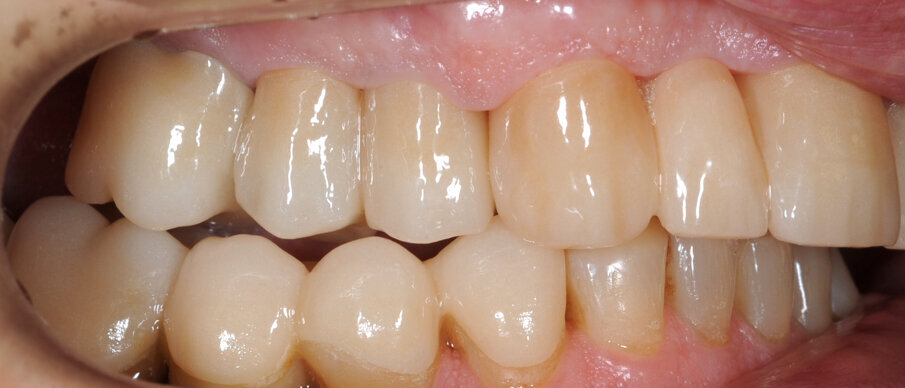

Il paziente utilizza questi secondi provvisori per otto settimane, durante le quali conferma la buona integrazione dei restauri e la soddisfacente funzione occlusale. Ciò è verificato con l’esecuzione di una nuova axiografia elettronica che già a due settimane dalla consegna evidenzia una buona risposta muscolare al nuovo design occlusale ed alla nuova postura mandibolare in TRP (Figg. 43-46). Provvediamo infine alle impronte per la costruzione dei manufatti definitivi in Zirconia-ceramica. I modelli sono scansiti in laboratorio con inEos X5 (Dentsply Sirona) su exocad (Figg. 47-49), ed una seconda scansione viene eseguita con i provvisori del Paziente posizionati sui modelli (Figg. 50-52). Il CAD consente di eseguire un matching fra le due scansioni, per cui i secondi provvisori utilizzati in TRP, con funzione occlusale sequenziale già completamente programmata, sono utilizzati per definire le morfologie dentali definitive di tutti gli elementi da restaurare (Figg. 53, 54) secondo il rapporto intermascellare definito (Figg. 55-58). Si esegue quindi fresatura al CAM della protesi definitiva in zirconia (Figg. 59, 60), la stratificazione e finitura ed infine la consegna al Paziente con cementazione in Panavia V5 (Figg. 61-65).